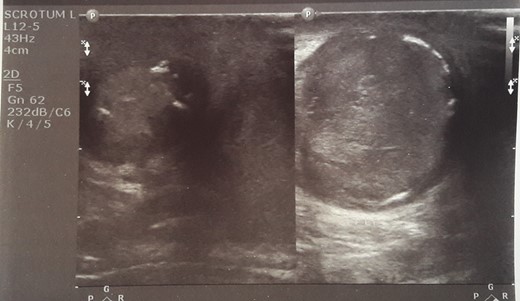

Initial sonographic findings were suggestive of epididymo-orchitis. The testis was well perfused and in normal position (Fig. 1). He was admitted for 3 days to start intravenous anti-inflammatory and antibiotic treatment and discharged under antibiotic treatment. Re-examinations were scheduled to assess treatment. On first reexamination, a week later, edema had subsided and the testis appeared hard, indurated and painless (Fig. 2). Ultrasound was still suggestive of epididymo-orchitis. Nevertheless suspicion for a testicular tumor was raised because of persistence of clinical and sonographic findings. An earlier appointment was scheduled this time. Five days later, at the second reexamination, another ultrasound showed reduced testicular perfusion that reached only the periphery of the testicular parenchyma (Fig. 3). The boy was operated as an emergency. Intraoperatively testis was non-twisted, with normal vas and vessels that ended in a necrotic testicular parenchyma. The testis was dark brown, hard on palpation and no blood came out when incised (Fig. 4). Right orchidectomy was performed. Since the exact cause of testicular necrosis was still unkown at the time of operation a left orchidopexy was performed to protect the only surviving testis from any future risk of torsion. The boy was discharged the next day. Histology showed a case of epididymitis nodosa and ruptured sperm granuloma that caused vascular compression, thrombosis and testicular necrosis (Fig. 5). More specifically, it showed proliferation of small ducts and gland-like structures in the walls of the vas deferens and epididymis in response to fluid and sperm dissection into the interstitium secondary to mechanical obstruction and increased intraluminal pressure. These findings are extremely rare in pediatric patients. The boy had an uneventful postoperative course and was discharged 2 days after surgery able to travel by sea to his home island.

On re-examination a week later, edema had subsided and the testis appeared hard, indurated and painless.